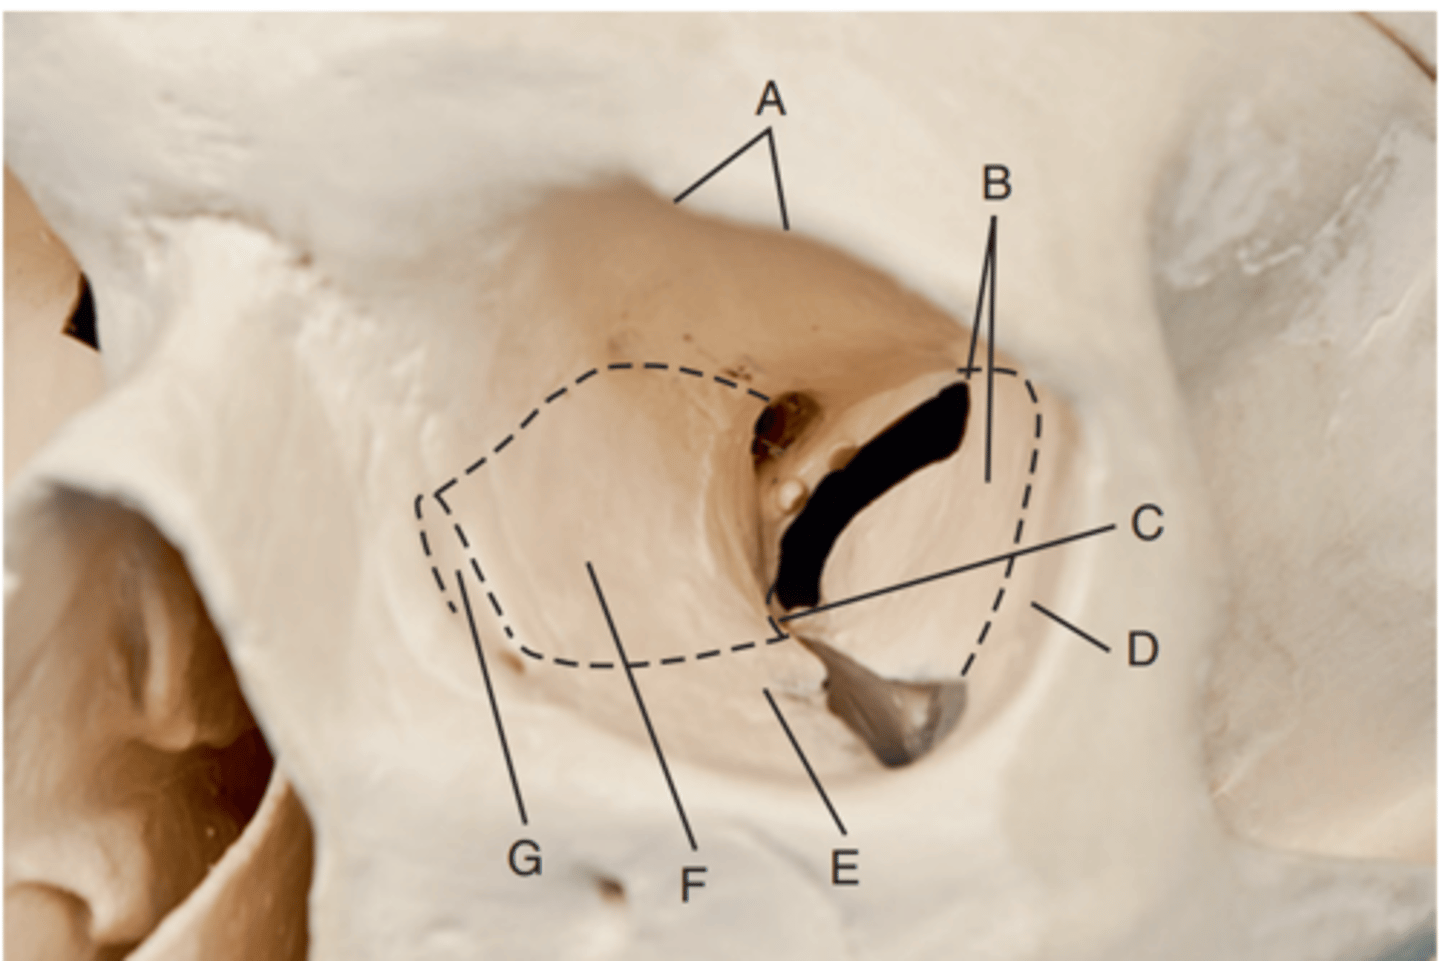

Optic foramen

Label A

Sphenoid strut

Label B

Superior orbital fissure

Label C

Inferior orbital fissure

Label D

Orbital plate of frontal bone

Label A

Sphenoid bone

Label B

Optic foramen and canal

Label C

Superior orbital fissure

Label D

Infraorbital margin (IOM)

Label E

Sphenoid strut

Label F

Lateral orbital margin

Label G

Supraorbital margin

Label H